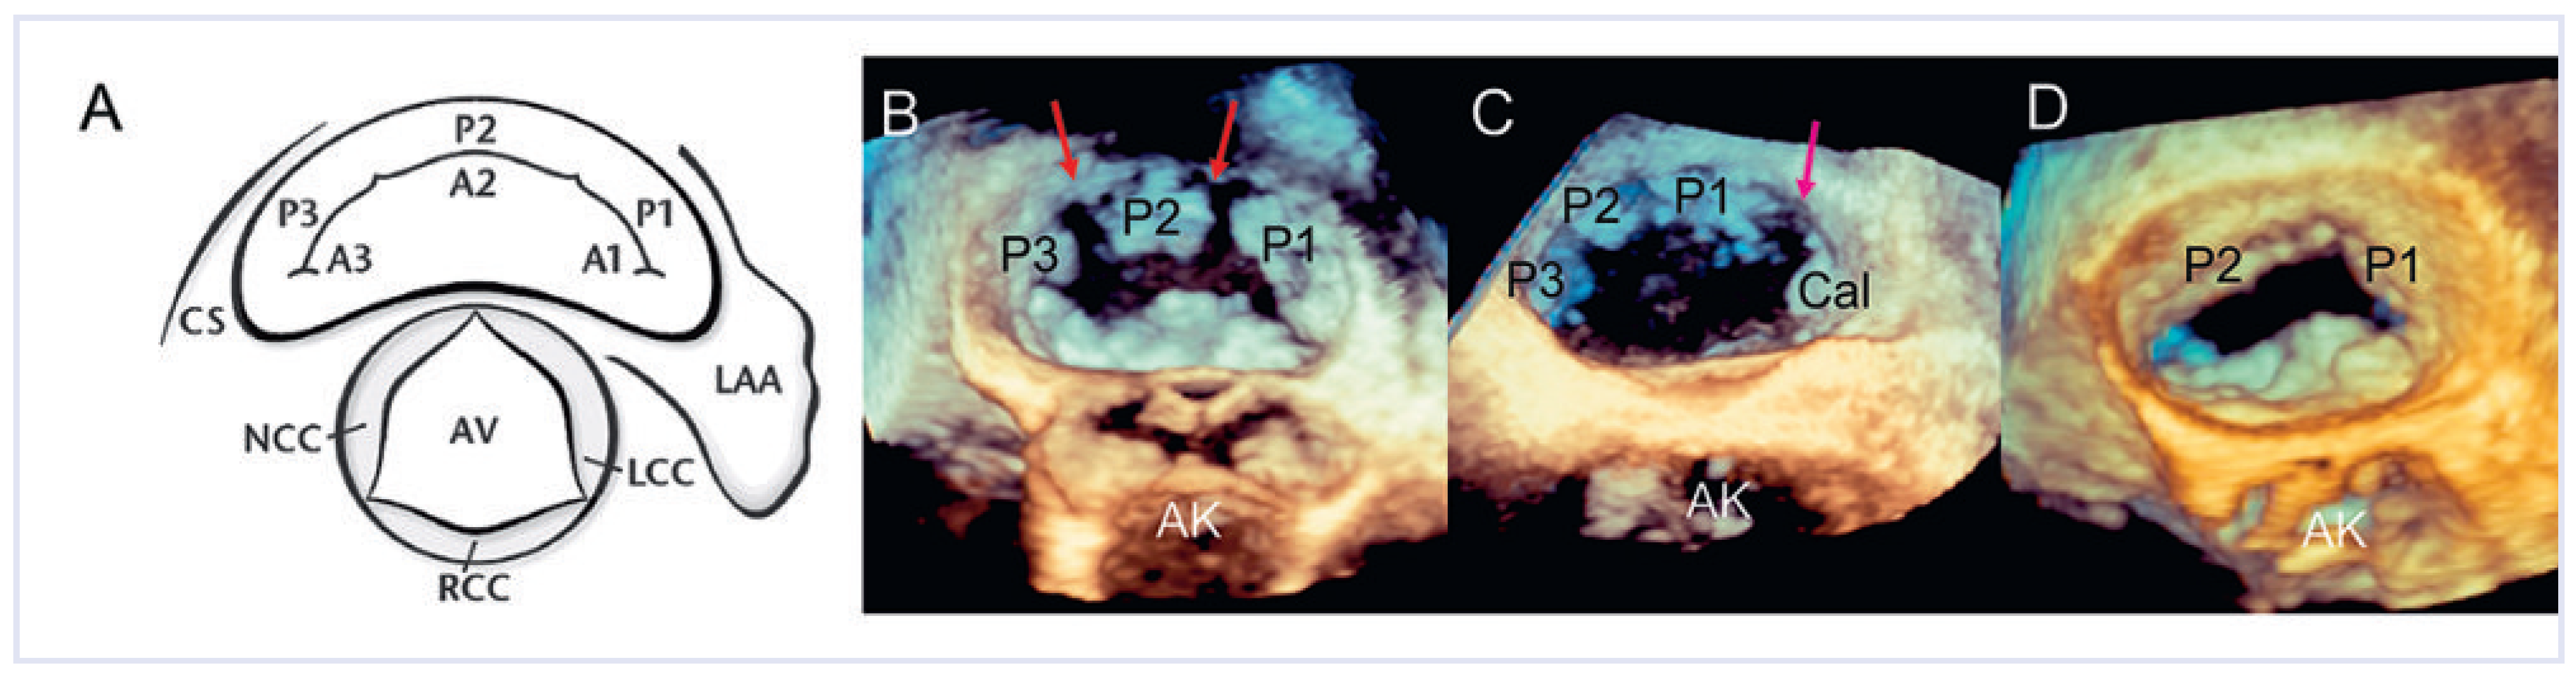

3DE zur Beurteilung der Nativklappe

3D-TEE